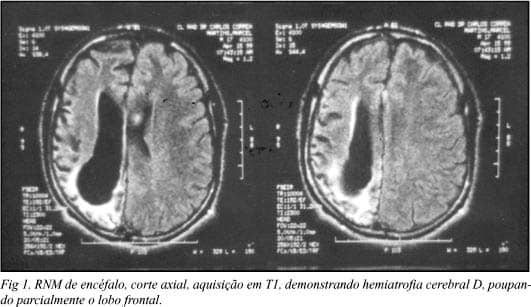

- Encefalite de Rasmussen: Epilepsia focal crônica progressiva de etiologia imunológica. Cursa com crises focais intratáveis (epilepsia partialis continua), hemiparesia progressiva e atrofia de um hemisfério cerebral na neuroimagem. O tratamento definitivo muitas vezes é a hemisferotomia funcional.